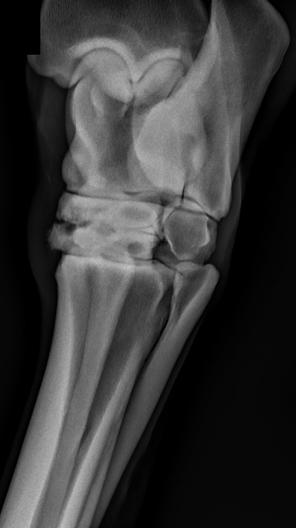

Pre-surgical radiograph showing each space that was to be resected. Post-op radiograph, showing the end result. Images courtesy of Ms. Sochan

Repeat radiographs were obtained, to track progression and for pre-operative planning. Radiographs showed narrowing of the inter-DSP spaces and significant bony remodeling (lytic and proliferative changes), associated with impingement of the DSP's. Four caudal thoracic inter-DSP spaces were severely narrowed and appeared to be touching or overriding. Two spaces cranial to these showed slightly better spacing but obvious bony remodeling, indicating that they are likely to contact each other during movement. It was decided to perform the DSP bone reduction technique on 6 spaces, the following day.

and movement improved gradually over the next several days and her anti-inflammatory dosing was decreased. 4 days after surgery, post-operative radiographs were obtained, confirming successful widening of the 6 involved spaces with no apparent complications. Her last doses of IV antibiotics were given, and she was discharged that same afternoon.